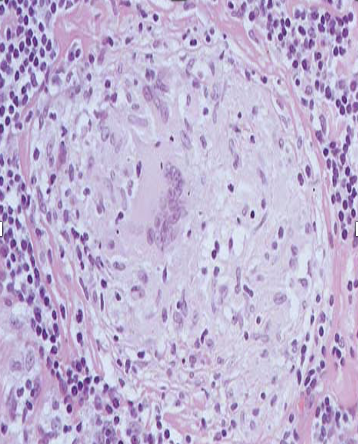

this is a presentation of

chronic pyogenic osteomyelitis

Identify what is 6 pointed by arrow

seen in case of chronic osteomyelitis

mixed inflammatory exudate

Q

Identify what is 5 pointed by arrow

bone trabeculae

what type of multinucleated giant cells are seen here

Langhan’s type of multinucleated giant cells